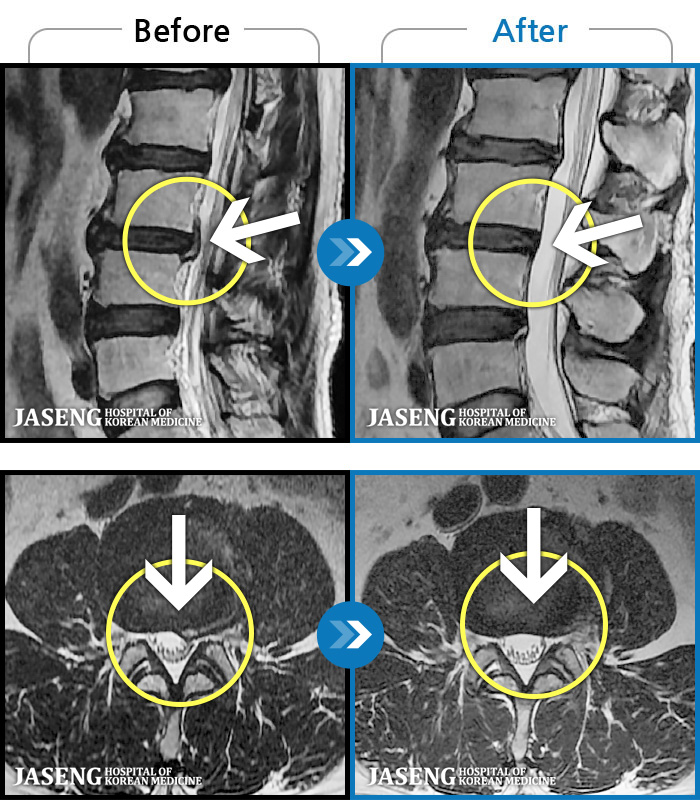

저는 협착증으로 병원에 입원해서 원장님께 치료 받고 있는 환자에요~

입원 전에는 다리가 저리고 땡겼는데 지금은 저림 증상은 거의 사라졌답니다

다 원장님 덕분이에요~~^^

항상 친절하고 최선을 다해 주셔서 너무너무 감사드리고 앞으로도 잘 부탁드립니다.